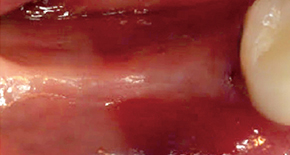

1. Before surgery